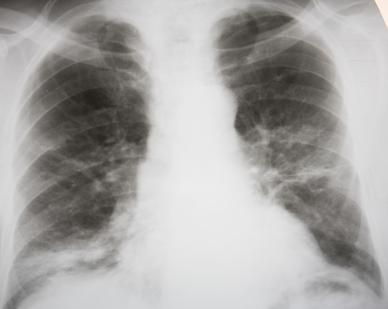

Ante estos síntomas, el médico determinará con radiografía que se trata de una neumonía y no de otra infección respiratoria, como una bronquitis. Los objetivos del tratamiento –los antibióticos no sirven para este tipo de neumonía– son mejorar la respiración con el uso de humidificadores y oxígeno, y prevenir la deshidratación. Por eso se recomienda ingerir abundantes líquidos, que ayudarán a expulsar la flema y las secreciones.